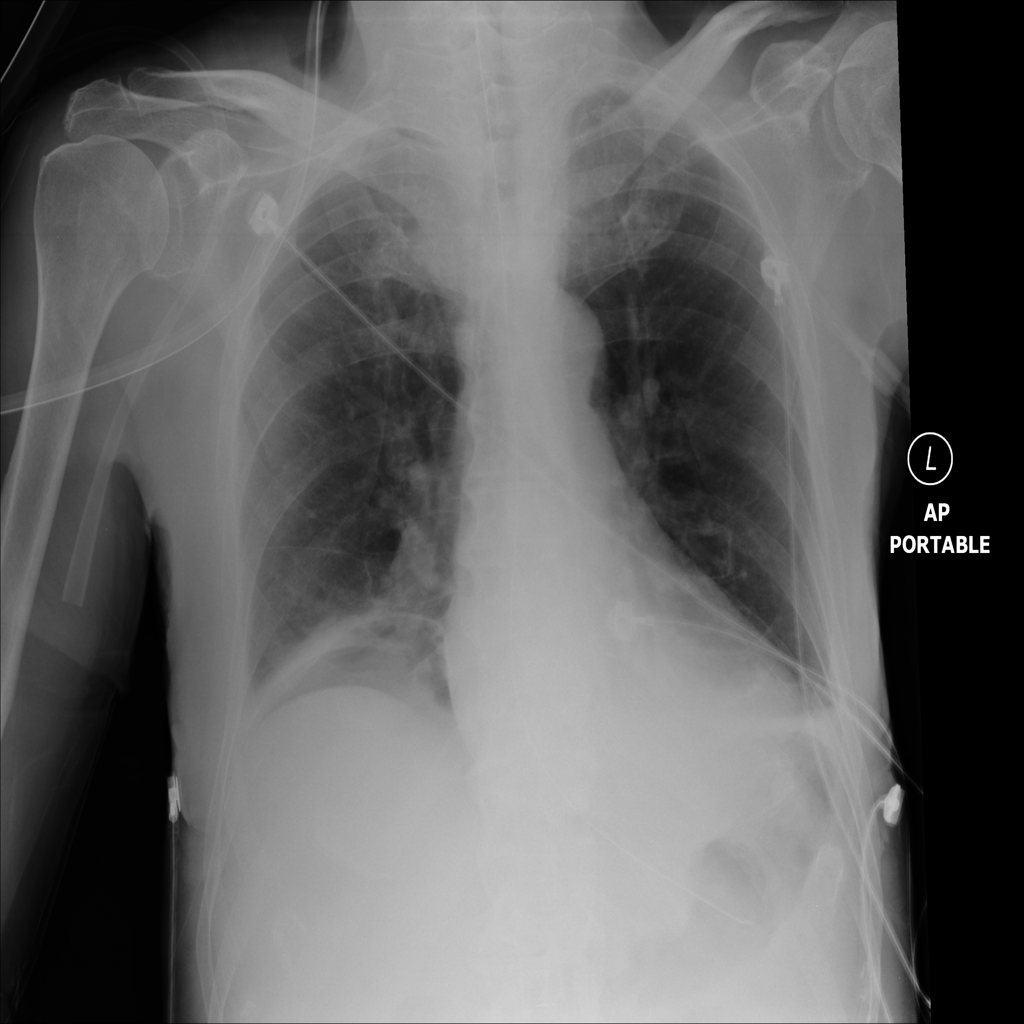

PAT-B625 · IMG-008Atelectasis

PAT-B625 · IMG-008

AP